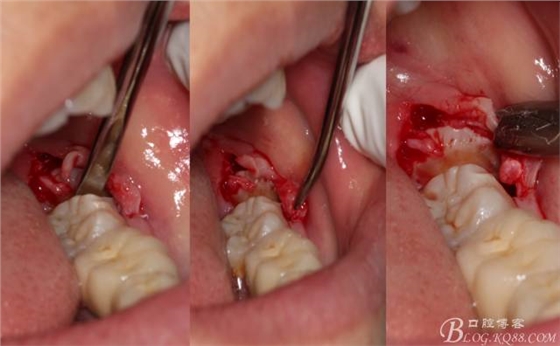

切開:角形切口,這個(gè)位置切開我喜歡更易操作12#刀。

640 (8).jpg

640 (9).jpg

鈍性翻辨露冠

640 (10).jpg

角度鍋輪機(jī)結(jié)合冷鹽水冷卻分冠

640 (11).jpg

分冠完成

640 (12).jpg

取出阻力部分冠

640 (13).jpg

在取出阻力冠后,嘗試性看能取出全部的牙體不,就是取不出也能整體撬動(dòng)牙根。